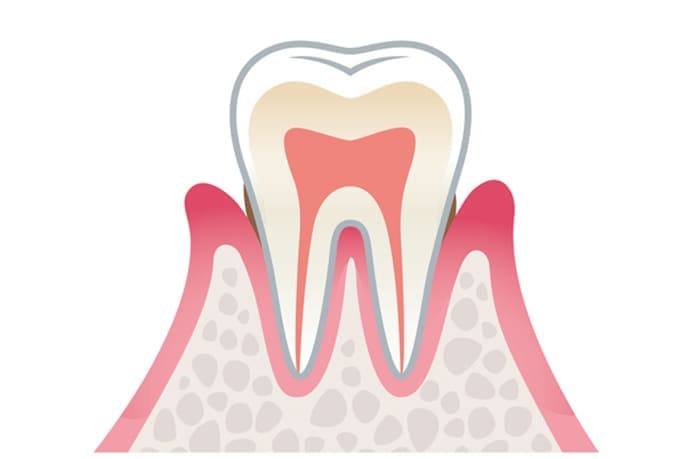

重度歯周炎 危険度★★★★★

重度の歯周炎になると、歯がグラグラして、歯と接している歯茎がさらに腫れ、化膿が進みます。歯と歯の間が広がり、歯茎が下がって、歯が長く見えます。

この段階の治療法は再生療法を用いて歯周組織の再生をはかることが多いです。しかし、ここまで進行すると抜歯になる可能性が高くなります。